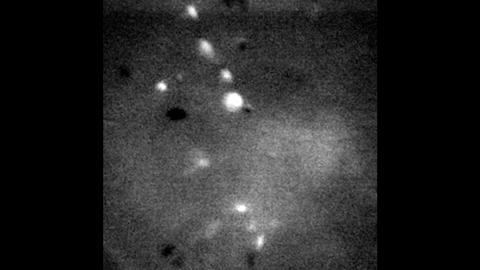

image: Example of imaging method used in research. Clip highlights normal, non-drinking activity.

Using cellular-resolution calcium imaging and miniature microscopes, the researchers tracked the luminescence of the activity in neurons during the very first time the subjects drank alcohol. The brighter and more active the neurons became, the less likely the subject would be to go on to develop compulsive drinking behaviors. In contrast, the neurons in drinkers predisposed for compulsive behavior quieted and decreased activity during drinking events.